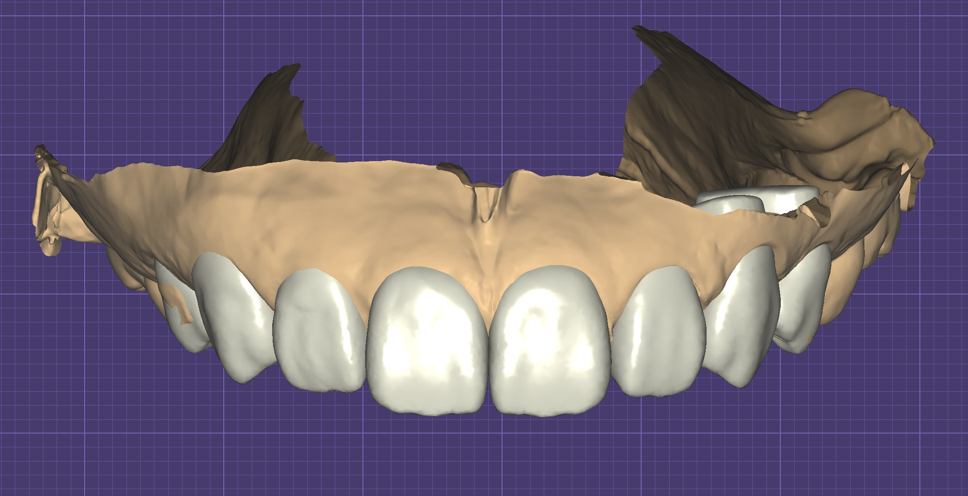

- 光學口腔掃描與電腦3D建模,如同單眼相機與高階攝影設備,精細度高且提供多面向檢視,可以當下確認立體模型正確性,降低誤差;

吳冠儒牙醫師的衡星診所與寬庭牙醫診所使用德國Cerec 3D數位系統,加上DSD (Digital Smile Design) 微笑曲線設計,先分析臉部與齒型,透過計算對笑容與成品進行模擬,再由診所內配置的牙技師團隊即時製作與調整,一天內將你對笑容的想像完成改造。

正規且美觀的牙齒貼片是透過一系列嚴謹且系統化的流程所製作出來,從詳細討論、攝影和口腔掃描開始,經過精密計算進行牙齒與笑容的模擬與細部調整,最後用齒雕機做出成品。